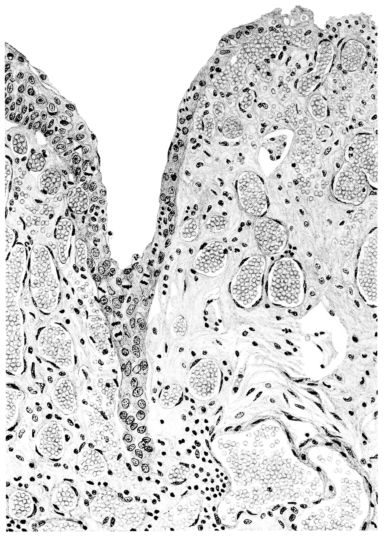

FIG. III. AUTOPSY NO. 90. DRAWING FROM A LESION OF THE TRACHEA (SOMEWHAT OLDER THAN THAT ILLUSTRATED IN FIGURE II). THE MUCOSA IS ENTIRELY LACKING. CONGESTION AND EDEMA ARE THE STRIKING FEATURES IN THE SUBMUCOSA. THE NECROTIZING PROCESS HAS EXTENDED INTO THE MUCUS GLANDS. THIS IS SHOWN IN THE LOWER PICTURE.

FIG. IV. AUTOPSY NO. 205. CONGESTION AND EDEMA OF THE SUBMUCOSA AND REGENERATION OF THE TRACHEAL EPITHELIUM.

The changes are less marked, perhaps, in the trachea than in its finer ramifications. The mucosa is constantly more or less destroyed and large areas, usually focal, are entirely devoid of their epithelial covering. This is replaced by a sparse exudate, composed largely of red blood cells, mucus, a small amount of fibrin, and nuclear fragments (Fig. II). It may dip into the submucosa for a short distance, but usually these indentures are associated with the ducts of the mucous glands into which the inflammatory reaction extends. A more striking feature than the exudate, however, is the edema and the congestion of the submucosa. The loose areolar tissue of the submucosa is spread widely apart, and throughout it distended blood vessels are very conspicuous. Occasionally such a vessel is broken and actual hemorrhage appears in the submucosa. Occasionally, too, the inflammation extends down the duct to the mucous gland itself, and here, also, aplastic inflammatory reaction is evident, inasmuch as the acini now stain intensely red with the cells undifferentiated from each other and specked here and there by broken remains of the dead nuclei (Fig. III). After the disease has continued for a short period, even at the end of five or six days, some regeneration of the epithelial lining may be seen (3) (Fig. IV). But despite this, the acute picture persists, and there goes on, side by side, an attempted repair characterized by epithelial regeneration and the same evidence of acute change. Since the lesion is essentially a superficial one, scars or contractures of any extent are not encountered in the trachea, even in examples of the disease that have ended fatally only after many weeks.[4]